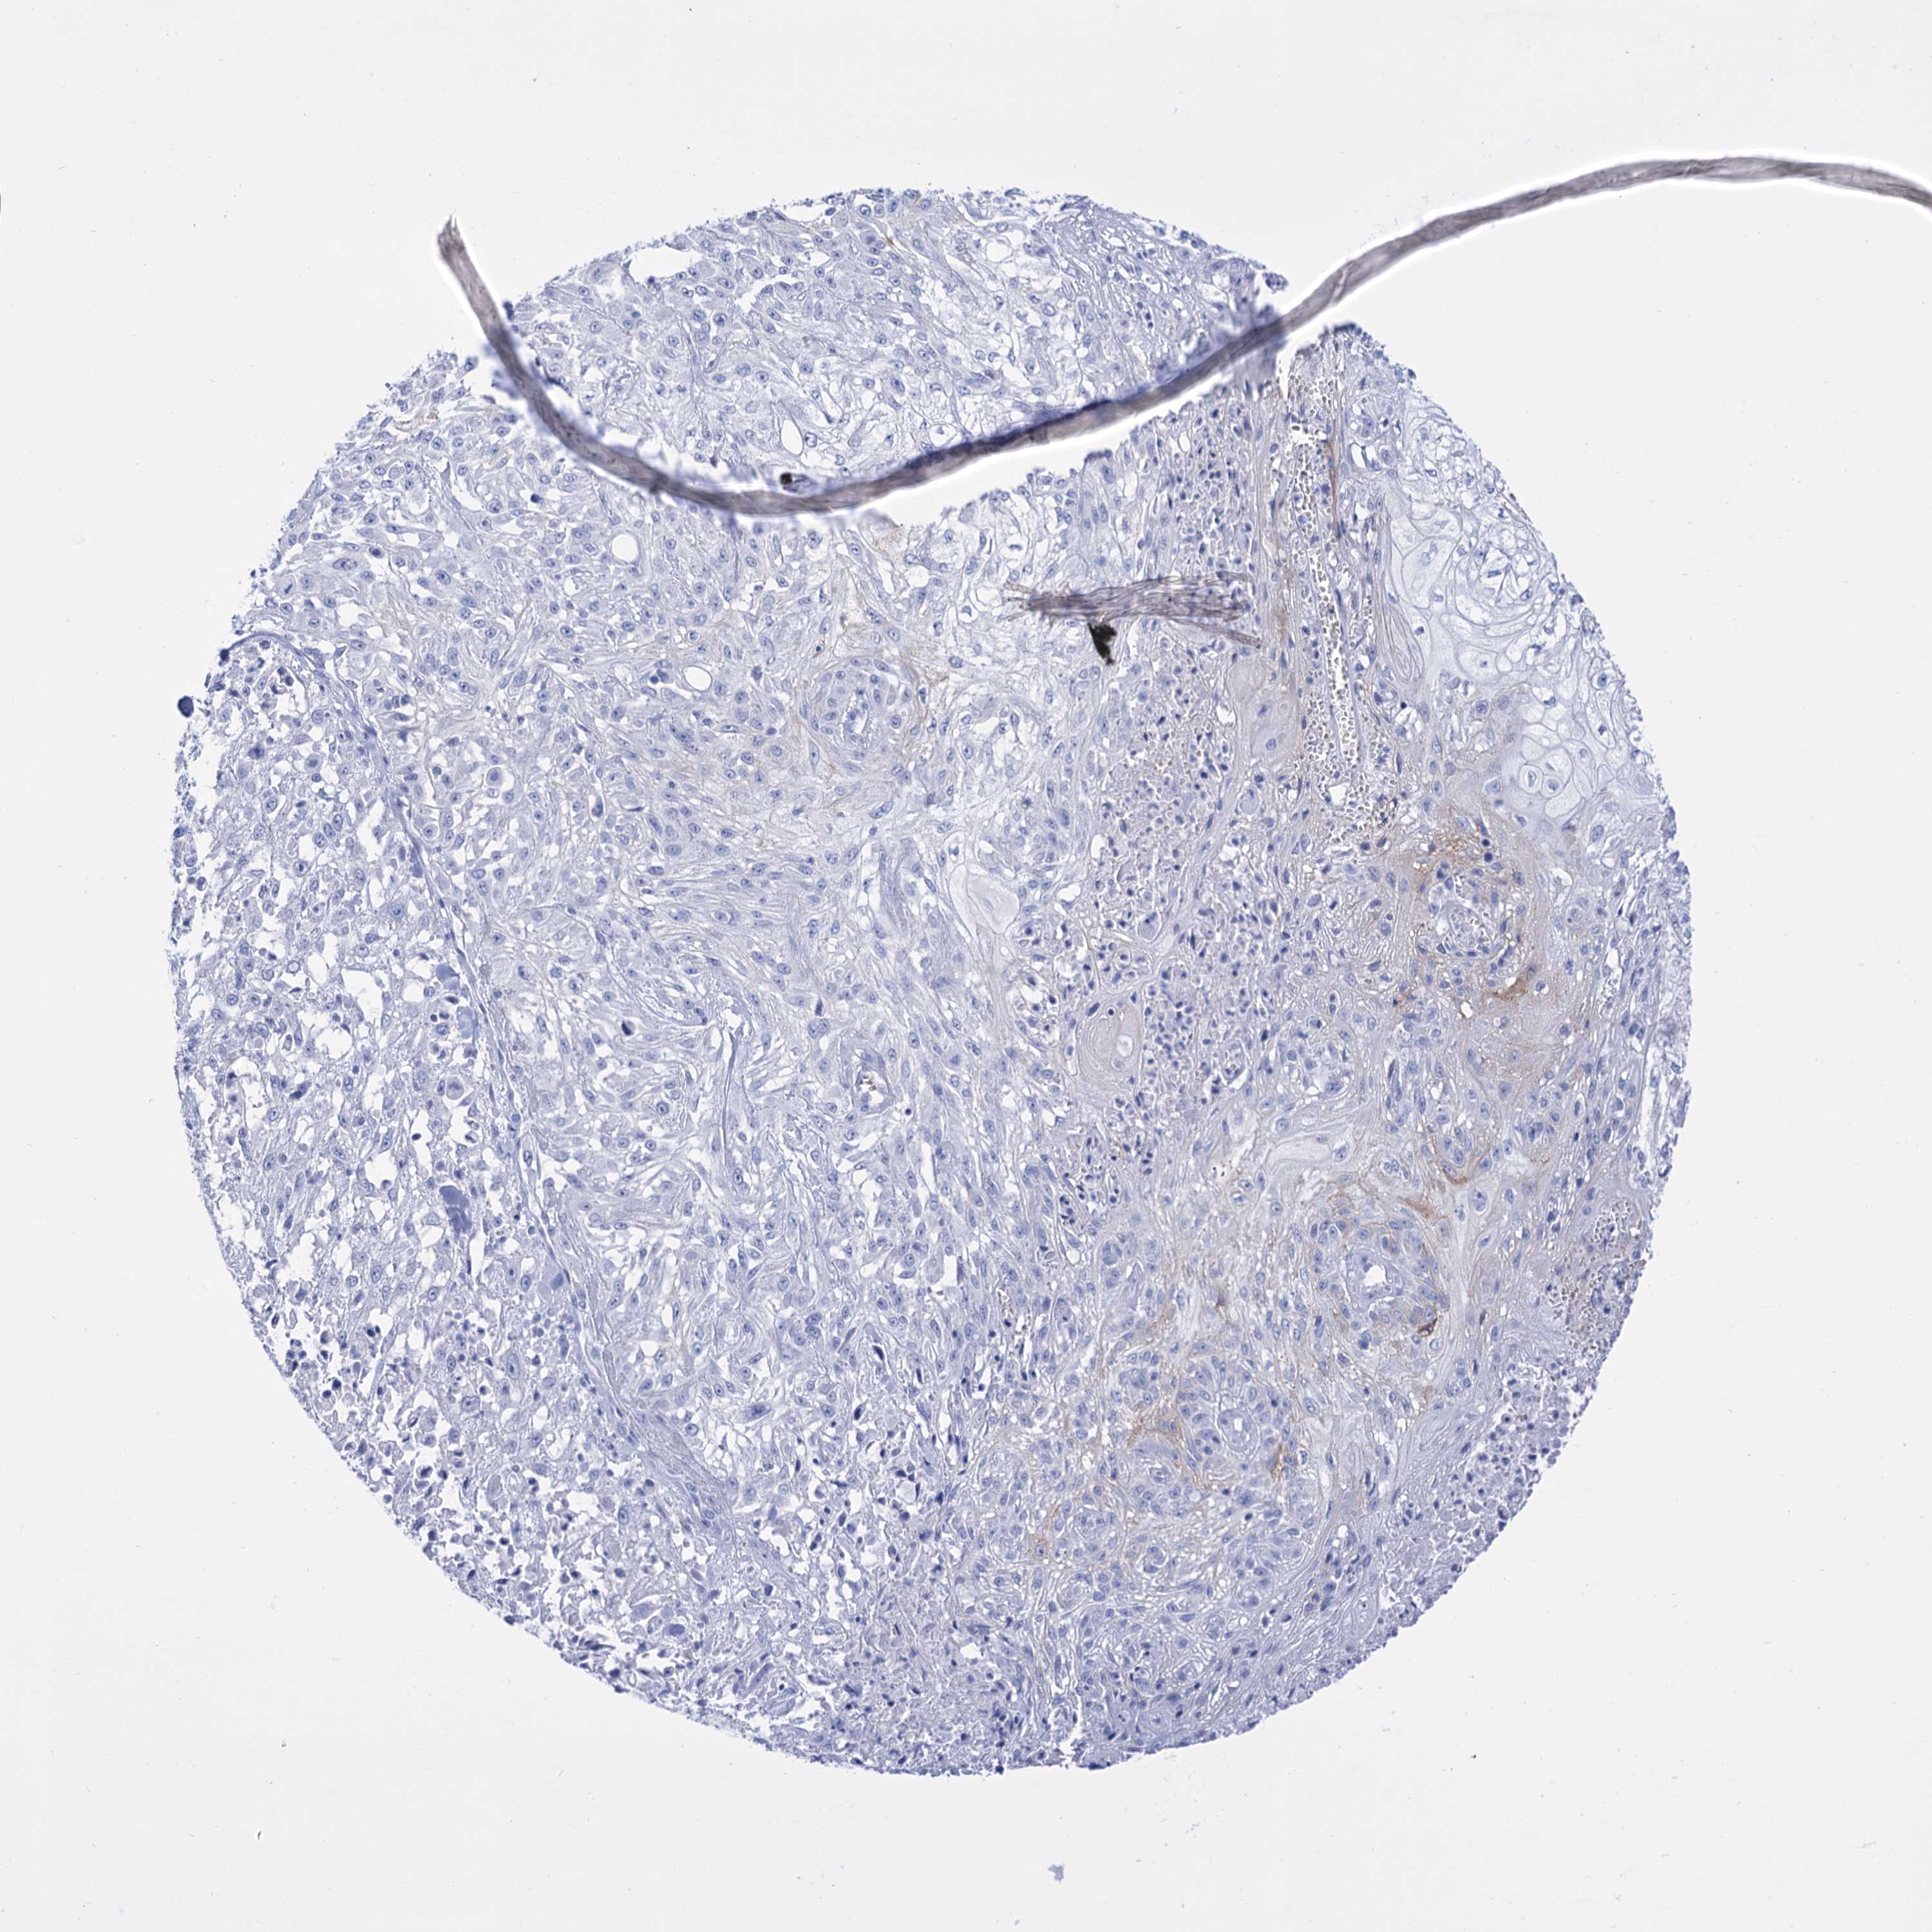

SKIN CANCER - Protein expressioni

A mouse-over function shows sample information and annotation data. Click on an image to view it in a full screen mode. Samples can be filtered based on level of antibody staining by selecting one or several of the following categories: high, medium, low and not detected. The assay and annotation is described here.

Antibody stainingi

Antibody staining in the annotated cell types in the current human tissue is reported as not detected, low, medium, or high, based on conventional immunohistochemistry profiling in selected tissues. This score is based on the combination of the staining intensity and fraction of stained cells.

Each image is clickable and will lead to virtual microscopy that enables deeper exploration of all samples and also displays staining intensity scores, fraction scores and subcellular localization as well as patient and tissue information for each sample.

Antibody HPA057610

Squamous cell carcinoma, NOS